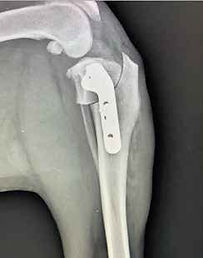

Chirurgie

Orthopédie